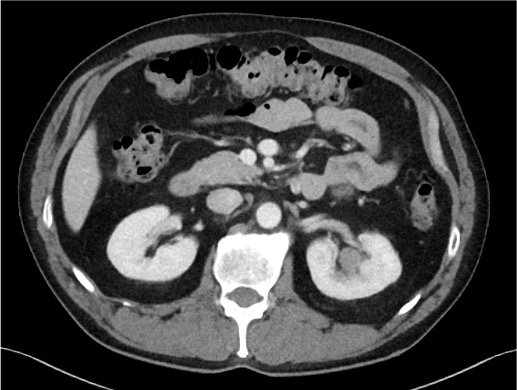

Efter utredning med scint och DT thorax/buk med i.v. kontrast konstaterades prostatacancer T4N1M1.

- M1: En 1 cm stor skelettmetastas i bäckenet.

I samband med undersökningen upptäcktes även ett bifynd, en 1,5 cm stor förändring i vänster njure med misstanke om lokaliserad urotelialcancer (UTUC) (T1N0M0).

Vid Diagnos

Vänster Njurbäckens tumör

Ny scint visar på regress av skelettmetastasen i bäckenet. Inga nytillkomna metastaser i skelettet. DT visar på regress av kända lymfkörtel- och skelettmetastaser. Dock påvisas en ny och liten sklerotisk metastas i L1.

Metastas i bäckenet